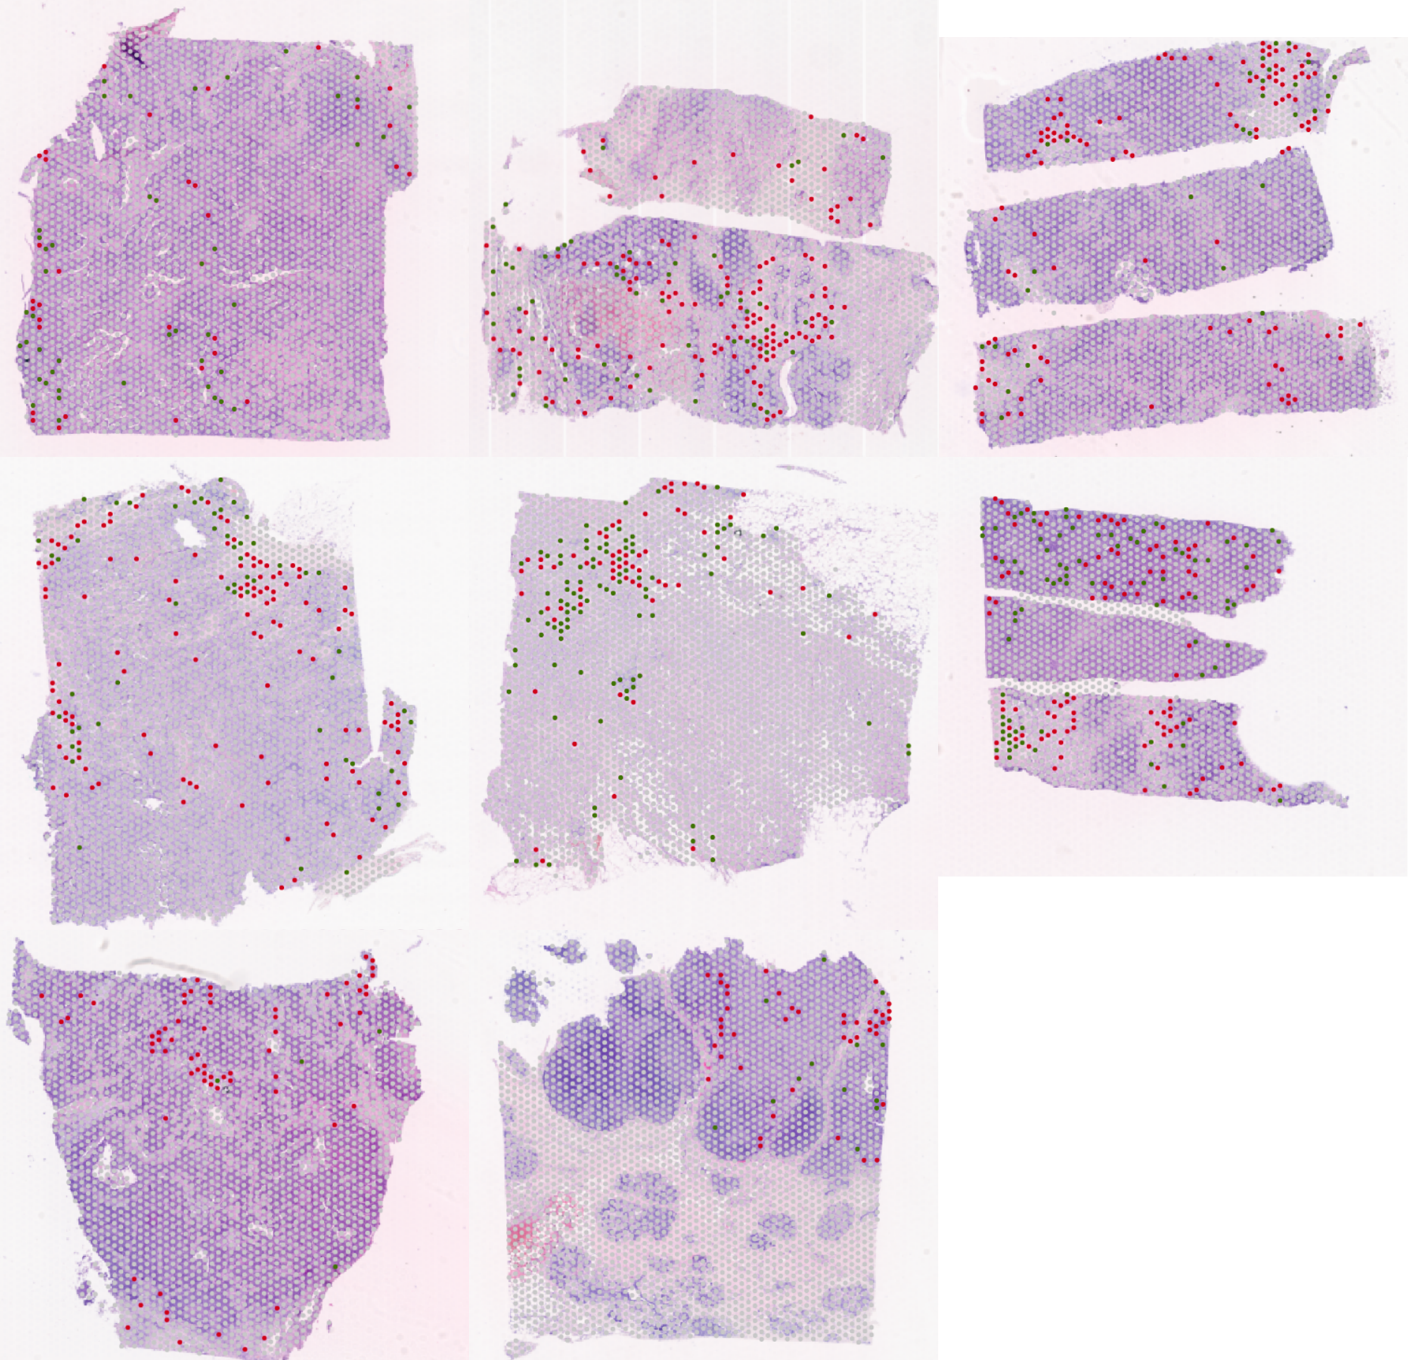

1. Рис. 1. Аннотация спотов в Loupe Browser (зеленые точки – стромальные CD68+ споты; красные точки – стромальные CD163+ споты). Примечание: рисунок выполнен авторами | |